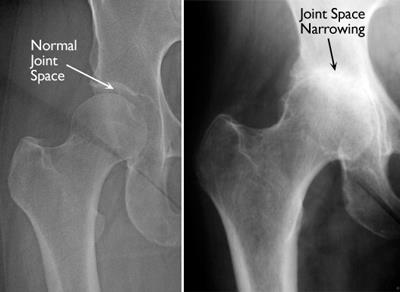

X-rays are imaging tests that create detailed pictures of dense structures, like bone. X-rays of an arthritic hip will show whether there is any thinning or erosion in the bones, any loss of joint space, or any excess fluid in the joint.

normal hip and hip with inflammatory arthritis

(Left) This X-ray shows a normal hip. (Right) This X-ray shows inflammatory arthritis with decreased joint space.